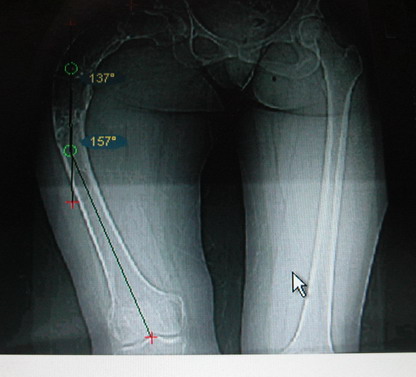

Моё мнение, что двойная остеотомия бедра с аппаратом Илизарова + Гексаподный механизм, или Тэйлора, В данной ситуации является методом выбора. Я очень извеняюсь за качество прилагаемых снимков, в которых я постарался отразить разницу междe одной и двумя остеотомиями бедра.